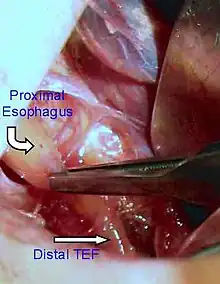

Treatments for the condition vary depending on its severity. The most immediate and effective treatment in the majority of cases is a surgical repair to close the fistula/s and reconnect the two ends of the esophagus to each other. Although this is usually done through an incision between the ribs on right side of the baby, a technique using three small incisions (thoracoscopy) is being used at some centers.[12]

Treatment of EA and TEF is surgery to repair the defect. If EA or TEF is suspected, all oral feedings are stopped and intravenous fluids are started. The infant will be positioned to help drain secretions and decrease the likelihood of aspiration. Babies with EA may sometimes have other problems. Studies will be done to look at the heart, spine and kidneys. Surgery to repair EA is essential as the baby will not be able to feed and is highly likely to develop pneumonia. Once the baby is in condition for surgery, an incision is made on the side of the chest. The esophagus can usually be sewn together. Following surgery, the baby may be hospitalized for a variable length of time. Care for each infant is individualized. It's very commonly seen in a newborn with imperforate anus.